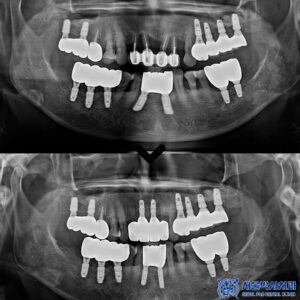

신흥동치과 앞니가 흔들려요. 뼈이식을 동반한 앞니 보험임플란트 치료 사례   많은 분들이 혈액순환을 돕는 약물, 특히 아스피린을 복용하고 계시는데요.   이런 경우에도 임플란트가 가능한지, 치료 과정은 어떻게 진행되는지 궁금해하시는 분들이 많습니다.   그래서 오늘은 실제로 저희 치과에서 치료를 진행하셨던 아스피린 복용 환자분의 사례를 통해 자세히 설명드리겠습니다.     위 환자분은 더보기…